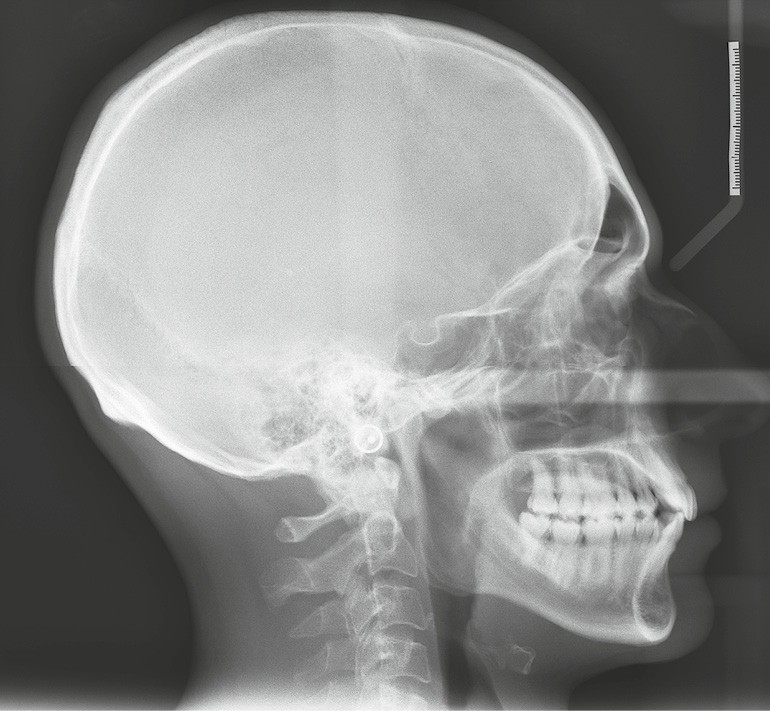

Diagnostic (fig. 1a-i)

Le patient consulte initialement pour des défauts d’alignement. L’examen clinique confirme l’existence d’un encombrement antérieur bimaxillaire, mais révèle aussi la présence d’une Classe II dentaire sévère, d’une exoclusion de la 27 et de troubles parodontaux (peu ou absence de papilles inter-dentaires). Sur le plan squelettique, le patient est relativement équilibré avec un profil harmonieux.